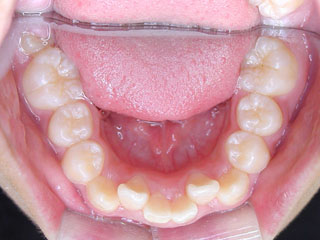

主訴:受け口 最近 左上の乳歯が抜けた

診断名:上顎左右側切歯先天欠如を伴う下顎前突

年齢:28歳

使用した主な装置名:マルチブラケット装置

抜歯/非抜歯および抜歯部位:非抜歯

治療期間:動的処置2年6か月、経過観察3年

費用の目安:90~140万円

リスク、副作用:マルチブラケット治療に伴う歯根吸収など偶発症が発生するリスクがある。

下顎前突が見られます。上顎の左右の側切歯(2番目の歯)は先天欠如でした。最近まで左上の乳犬歯が残っていた跡が見られます。下の歯は叢生も見られません。先欠の対応では素直に考えて人工的に歯を補う補綴処置が第一選択肢になります。矯正治療では、しばしば抜歯を行う事が多いので、先欠が在れば、その他の歯を抜歯して解決する事も多いですが、この方の場合は非抜歯の計画に致しました。

非抜歯での治療になりましたので、上顎の中切歯と犬歯の間に側切歯のスペースを作っている所です。もともと歯が無かったために、前方にも側方にも歯槽骨が少なく傾斜移動が多いので慎重な移動が求められます。